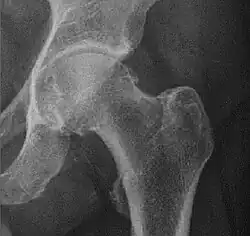

X-ray of hip dysplasia

![Normal hip.[3]](./_assets_/X-ray_of_measurements_on_a_normal_hip.jpg)

![Hip dysplasia.[3]](./_assets_/X-ray_of_measurements_in_hip_dysplasia.jpg)